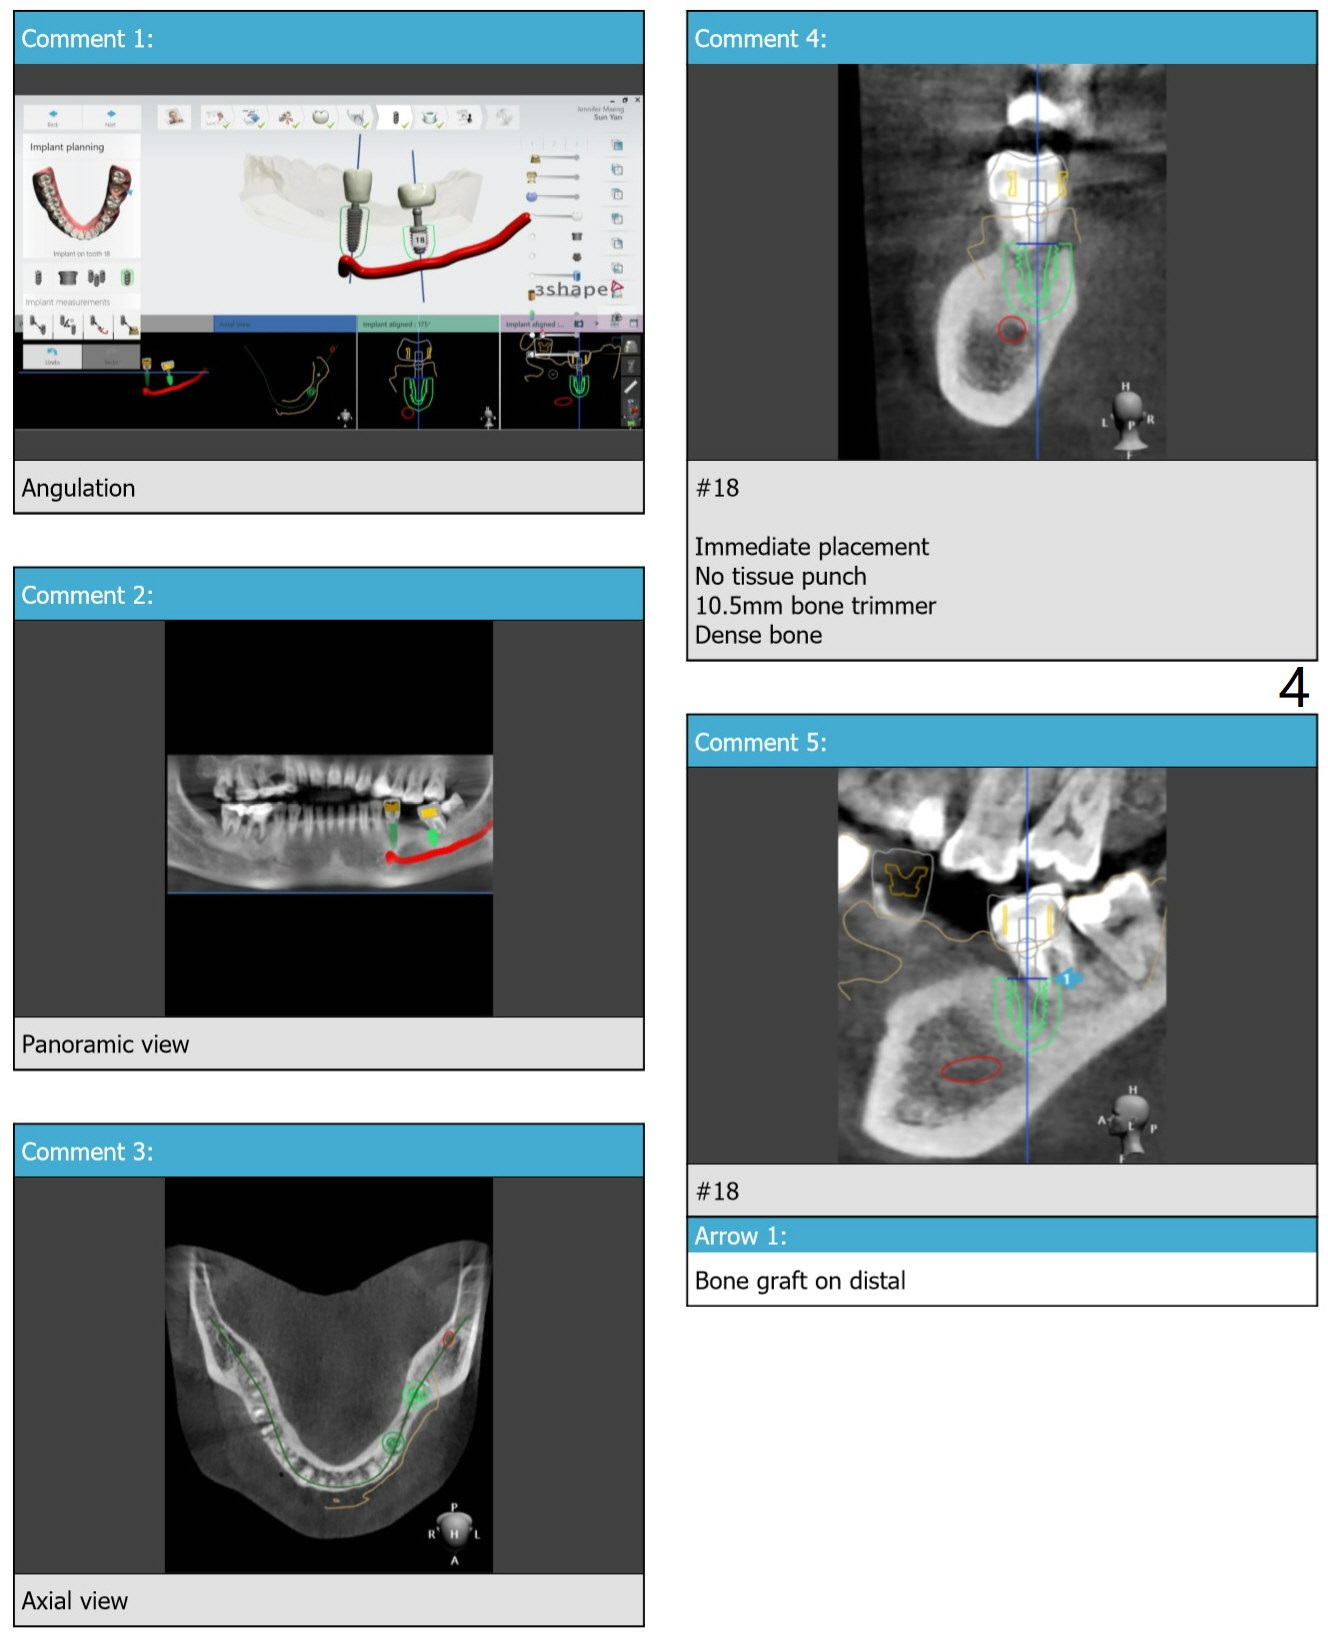

To avoid drill and implant deviation buccally due to the hard lingual plate at #20, use 4.0 mm cortical drill after 3.5x7.3 mm drill. Then resume the normal drill sequence. After implant placement, make sure that they are placed deep enough clinically and radiologically. FC